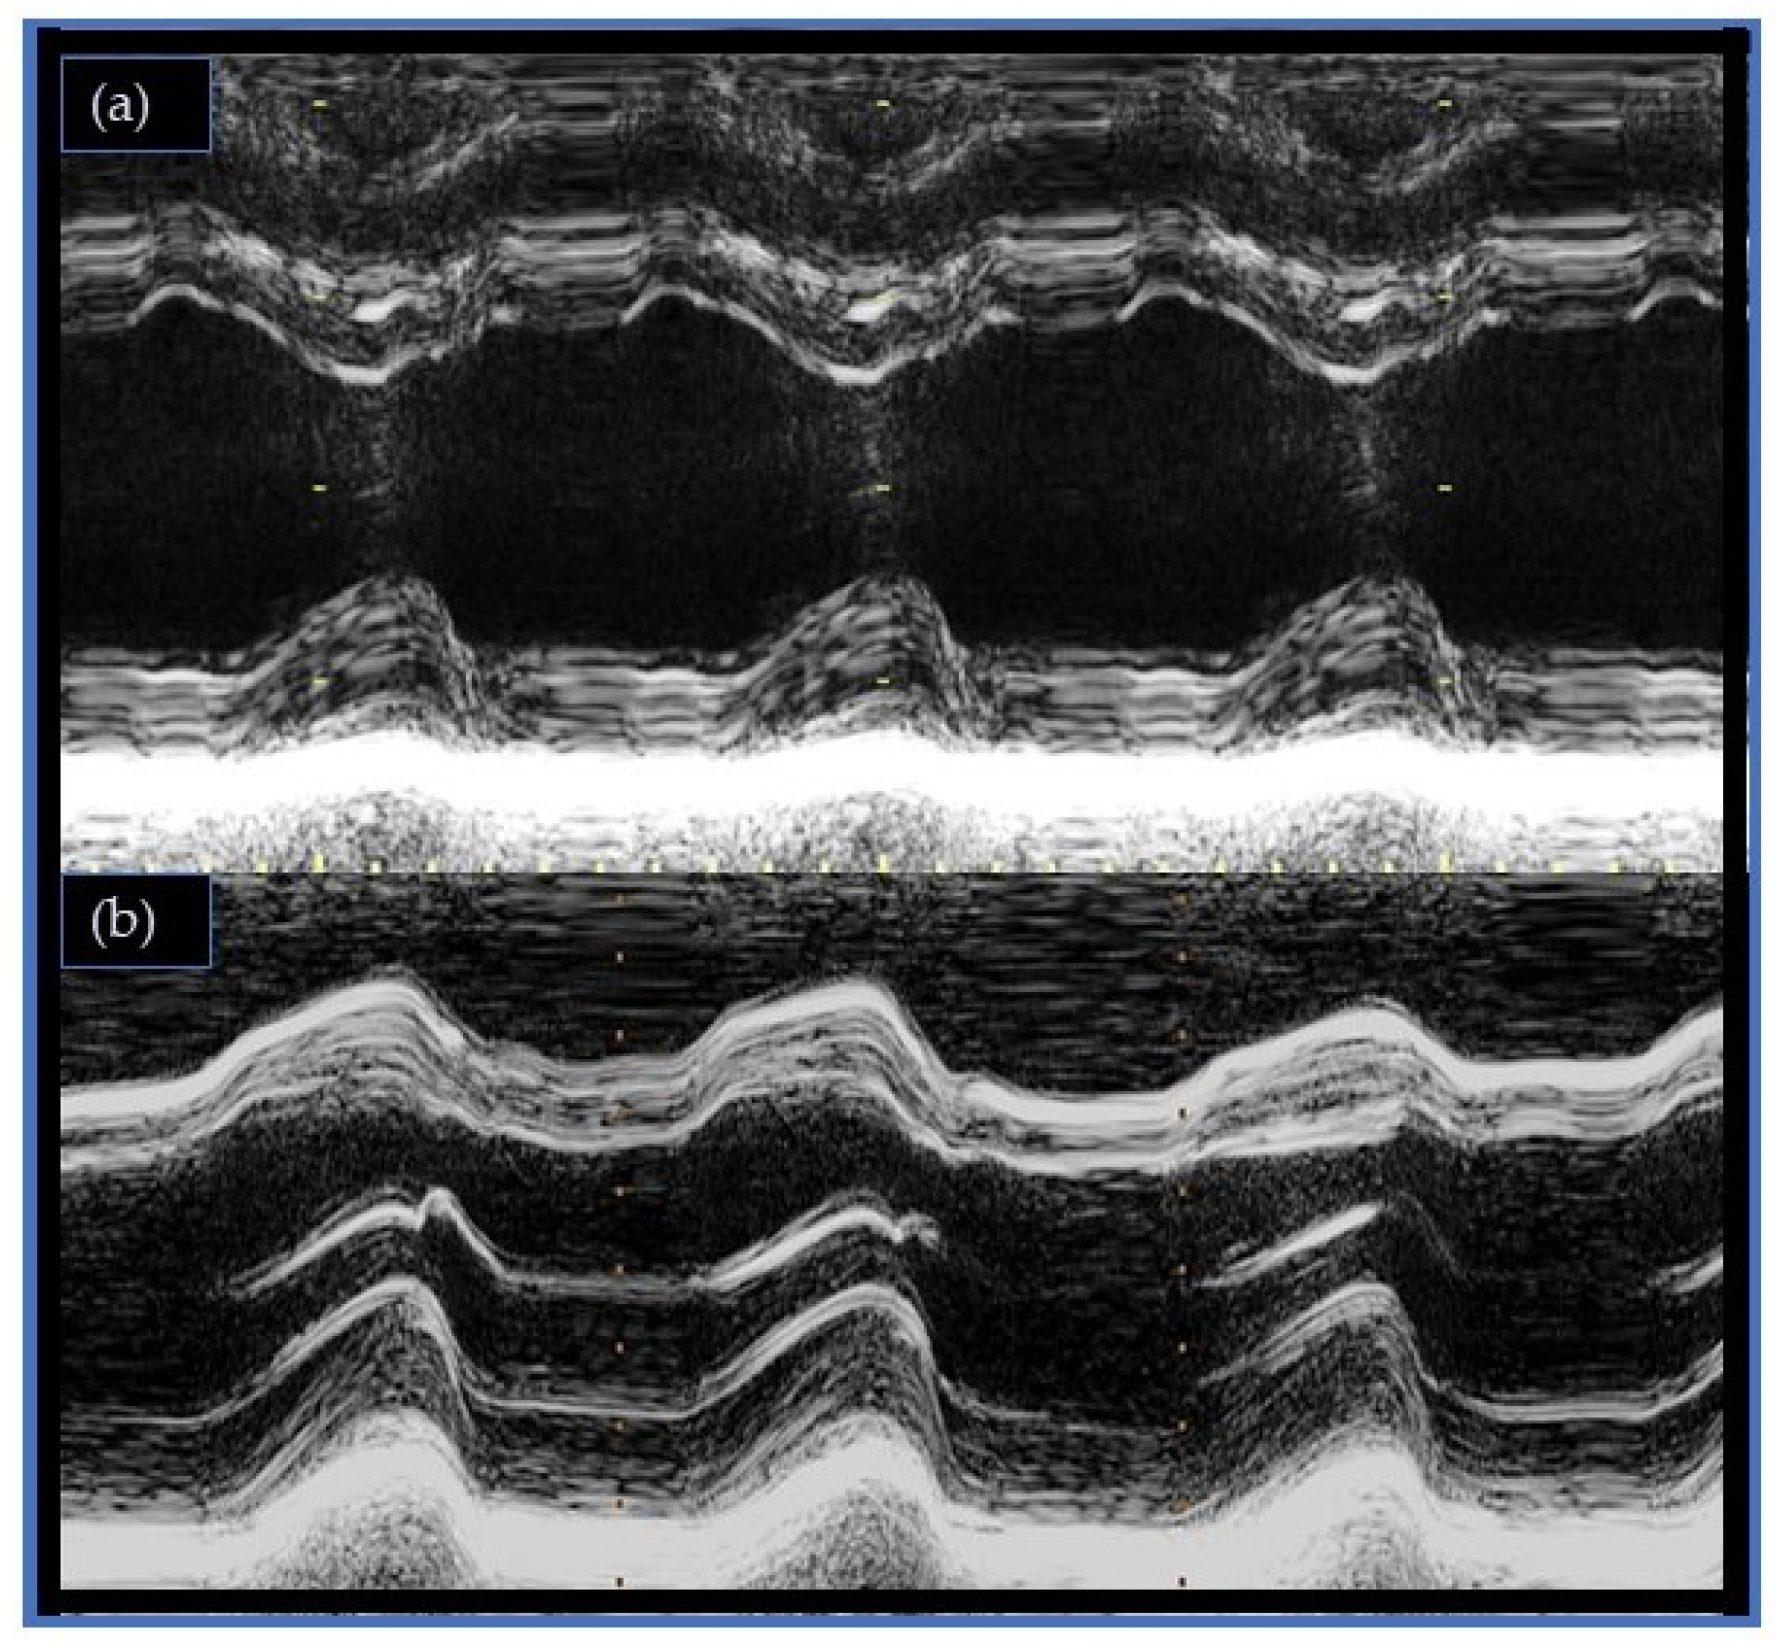

The IVS represents the keystone for interventricular coupling and the biventricular performance [27,48]. Unlike the other ventricular walls, IVS is directly exposed to both intraventricular pressures and influenced by the systolic and diastolic trans-ventricular gradients. Under normal conditions, it thickens during systole, increases its curvature, moves towards the LV center, and returns to its original position during diastole [49]. Breathing patterns can influence IVS motion during diastole, with inspiration displacing it posteriorly and expiration moving it in the opposite direction. This breathing-related effect on IVS motion is minimal under normal circumstances but can be more significant in pathological conditions [8,19]. When the IVS moves in the opposite direction to the physiological motion, it is called a “paradoxical” septum (Figure 1). A differential diagnosis is important for interpreting other paradoxical septa (Table 2) [50], but a comprehensive discussion of them is beyond the scope of this review.

Figure 1. (a) Normal septal motion pattern (b) Postoperative paradoxical septal motion (Motion-mode imaging).